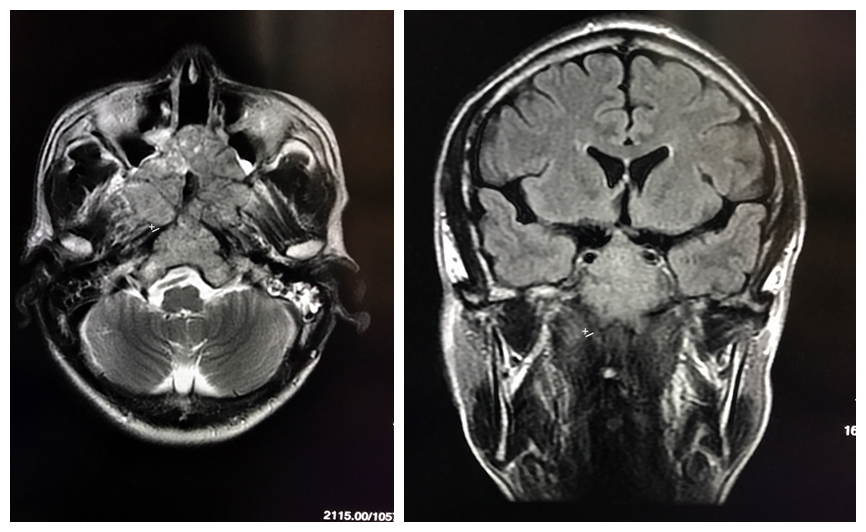

颅底脊索瘤(五):影像特点

脊索瘤是一种较为少见的肿瘤,呈缓慢的侵袭性生长,可以发生在颅底斜坡

脊索瘤的治疗:颅内脊索瘤多发于中线颅底部位,手术完全切除困难.